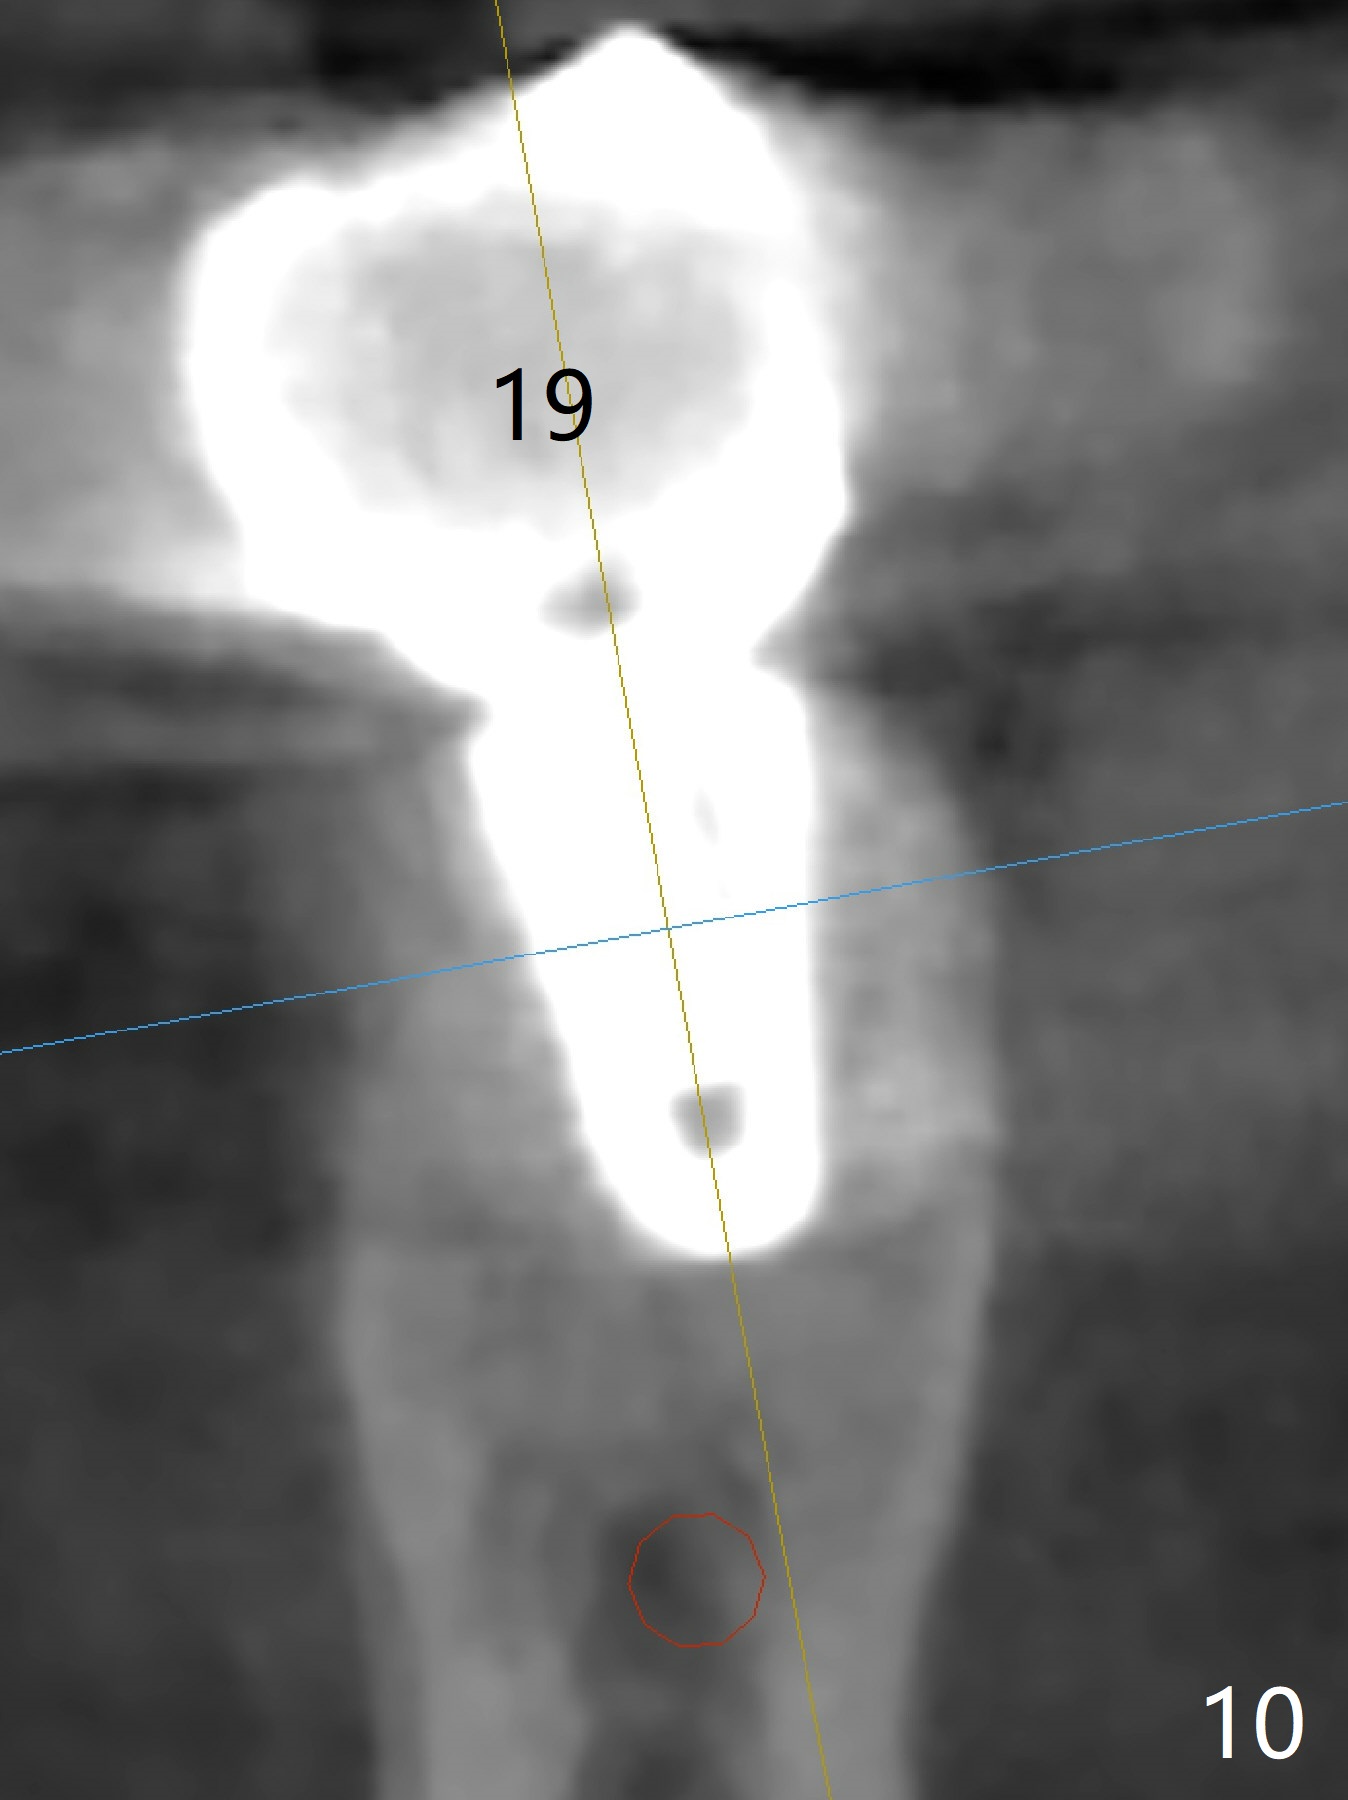

Five months post cementation, the patient reports that #18 implant is loosening. It appears that the implant has to be redone, placed deeper (Fig.3). There is still bone apically. Encourage smoke cessation, better oral hygiene and implant placement at #2. He is a bruxer.

Five months post cementation, the patient returns because of loose abutment screw at #18. Bone resorption is noted (Fig.7 arrowheads). His oral hygiene is fair. He refuses implant at #2, saying that he dares not to chew on the left. When the screw became loose again 3 months later, he accepted the treatment. While he was returning to his home country, the lower right bridge was sectioned and the tooth #30 was removed. He is thinking of 2 implants at #29 and 30 (Fig.8). Bone loss appears not to get worse at #18-20 (Fig.9-11 (CBCT coronal sections, 2 years 7 months post cementation)). The implant at #19 is loose with a gap between the implant and the bone 3 years 5 months post cementation (Fig.12 *). SM implant does not last under stress (bruxism) and rigid implant/abutment connection.